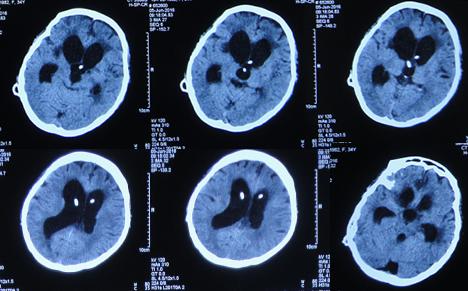

第1家医院治疗13天后即2015年8月16日,查头CT:双侧侧脑室,三脑室及四脑室扩张(图-4),且给予腰穿检查,提示颅压高(脑脊液检查结果不详),给予相关对症治疗。

图-4:2015年8月16日头部CT

第1家医院治疗16天后即2015年8月19日,间断头痛,腰穿颅内压仍高,查头部CT示脑室进一步扩张(图-5)。

图-5:2015年8月19日头部CT